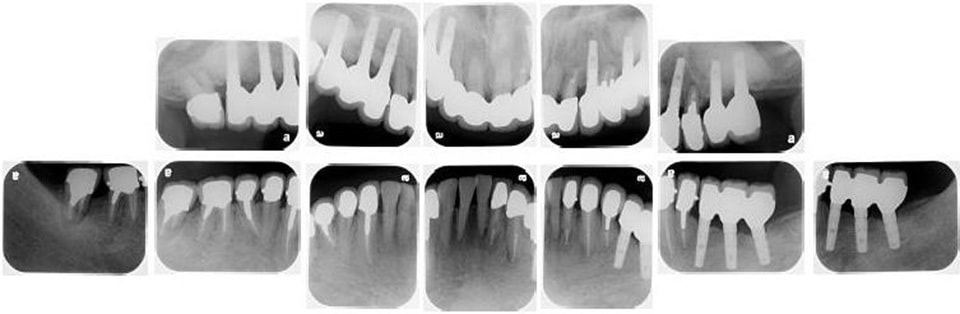

治療後レントゲン

奥歯をインプラントにて治療し、よく噛めるようにしました。また、虫歯や歯の根の治療のやり直しを行いセラミックにて審美的に修復しました。

どんな治療にもメリット・デメリットがあります。患者さんの年齢や口腔内の状態、さまざまな要因で、治療のメリット・デメリットの大きさは、変わってきます。患者さんの状態によって、受ける治療のメリット・デメリットは異なるので、治療を受ける際は、よく説明を受けられてからの方が、安心して治療を受けることが出来るかなと思います。

インプラントや入れ歯、ブリッジもそれぞれメリット・デメリットがあります。